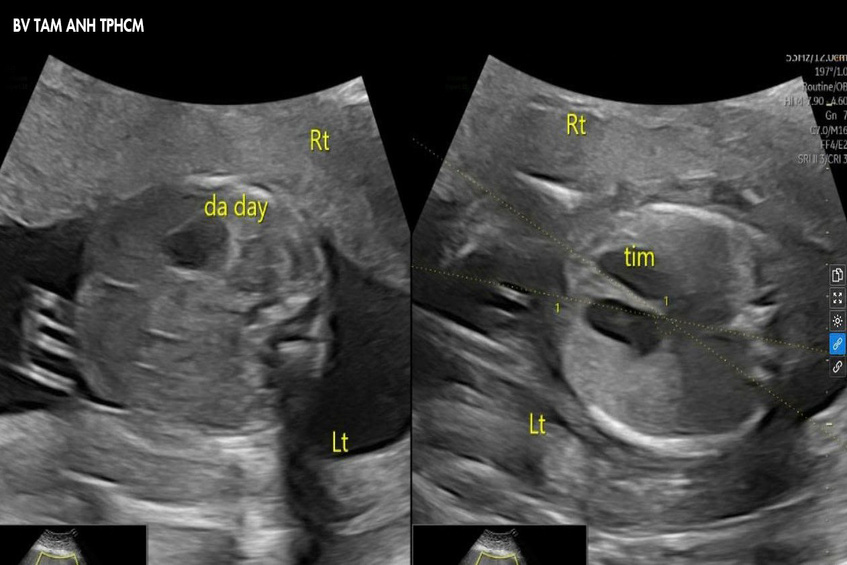

ThS.BS Nguyễn Thị Liên Phương, chuyên khoa Y học bào thai, siêu âm phát hiện tim và dạ dày thai nhi nằm ở bên phải (bình thường ở bên trái), biểu hiện của đảo ngược phủ tạng. Đây là tình trạng các cơ quan trong cơ thể nằm ngược lại so với vị trí giải phẫu bình thường.